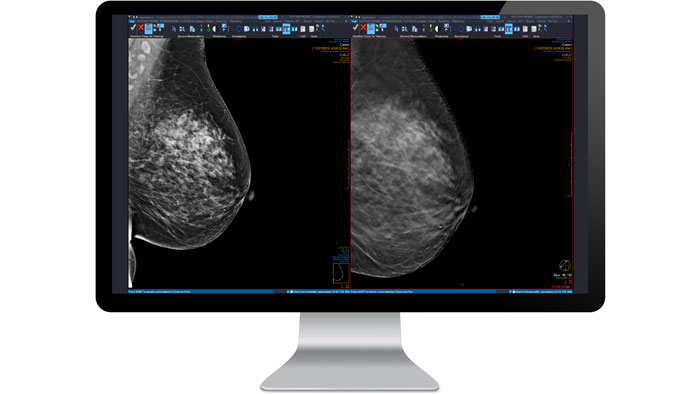

Mamografía

Analice mamografías tradicionales, ecografías mamarias, RM de mama, tomosíntesis digitales de mama (DBT) y estudios radiográficos generales, todo desde un único escritorio. El posicionamiento y la unificación de tamaño automáticos facilitan la comparación de imágenes de exámenes anteriores y diferentes modalidades sin necesidad de recurrir a la manipulación manual.

Simple

Visualice imágenes de diferentes modalidades y proveedores en un único escritorio: mamografías, tomosíntesis digitales de mama, estudios radiológicos generales y datos no DICOM.

Optimizada

Reduzca el tiempo y la fatiga al realizar lecturas gracias a herramientas de diagnóstico líderes en el sector, protocolos configurables por el usuario y posicionamiento y ajuste de tamaño automáticos para la comparación de diferentes modalidades y exámenes previos.

Potente

Mejore la fiabilidad del diagnóstico gracias a la asistencia durante la tomosíntesis digital de mama, la detección asistida por ordenador, las líneas de referencia cruzada entre zonas sospechosas en varias vistas y las alertas para las imágenes no interpretadas.

Funciones y ventajas

Compatibilidad multimodalidad

El módulo de mamografía admite PACS multimodales y de terceros, con acceso completo a imágenes en un única estación de trabajo. Examine y diagnostique con fiabilidad gracias a nuestros protocolos de visualización inteligente configurables por el usuario que permiten un flujo de trabajo automatizado, nuestro conjunto de herramientas de mamografía líder en el sector, detección asistida por ordenador y comparación optimizada de varios exámenes previos.

Tomosíntesis digital de mama (DBT)

Agilice los flujos de trabajo, optimice las comparaciones y mejore la fiabilidad del diagnóstico gracias a un amplio conjunto de herramientas integradas para mamografías 3D de dosis baja. El módulo de tomosíntesis digital de mama de Vue Mammo incorpora capacidades de flujo de trabajo exclusivas y herramientas especializadas que optimizan la interpretación de las tomosíntesis digitales de mama y otros procedimientos.

Compatibilidad con cribado complejo

Muévase rápidamente de un estudio al siguiente con un ratón o un teclado inteligentes.

Ecografía mamaria completa (ABUS)

Como parte de Philips Clinical Collaboration Platform, Breast Imaging Module se presenta como una solución versátil que permite a los médicos analizar mamografías digitales, ecografías mamarias, ecografías mamarias automatizadas (ABUS), exámenes radiológicos generales o tomosíntesis digitales de mama (DBT) desde un único escritorio.